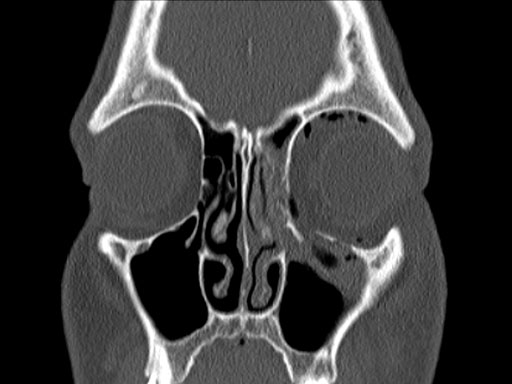

The complex geometry of the bony orbit makes precise anatomical reconstruction somewhat challenging, particularly in cases of two wall fractures and when the deep orbital cone is affected. The new matrix orbital set was developed to address the need to have all necessary implants and instruments available for all types of fractures in this area.

Based on the matrix midface system, it is a dedicated set with implants and instruments specifically designed intended for orbital reconstruction. It includes a variety of existing implants, such as the orbital floor mesh plates in two versions (0.3 mm and 0.4 mm in thickness) as well as the curved 12-hole orbital plate, and the straight adaption plate with 20 holes. All implants match the sizes and hence the color coding of the matrix midface system being available in 0.5 mm (blue), 0.7 mm (pink) versions.

Furthermore, as orbital floor fractures are quite frequently associated with medial wall fractures, anatomical restoration, especially in the transition zone between both walls, is a demanding procedure. As described by Hammer [1], the orbital floor has an initial shallow convex section behind the rim, then inclines upward behind the globe, and inclines upward to meet the medial wall, creating a distinct bulge behind the globe. These convex curves of the medial wall and floor create a postbulbar constriction of the orbital cavity, which must be reconstructed when the orbit is rebuilt following fractures. Treatment is directed at precise anatomical reconstruction of orbital shape and volume in order to restore the correct position of the eye. To provide surgeons with an adequate implant that addresses the requirements of two wall acute orbital fractures or for secondary reconstruction of enophthalmos and dystopia, a new series of preformed orbital plates was developed for the new orbital matrix system.

Fig 1 Matrix orbital set.